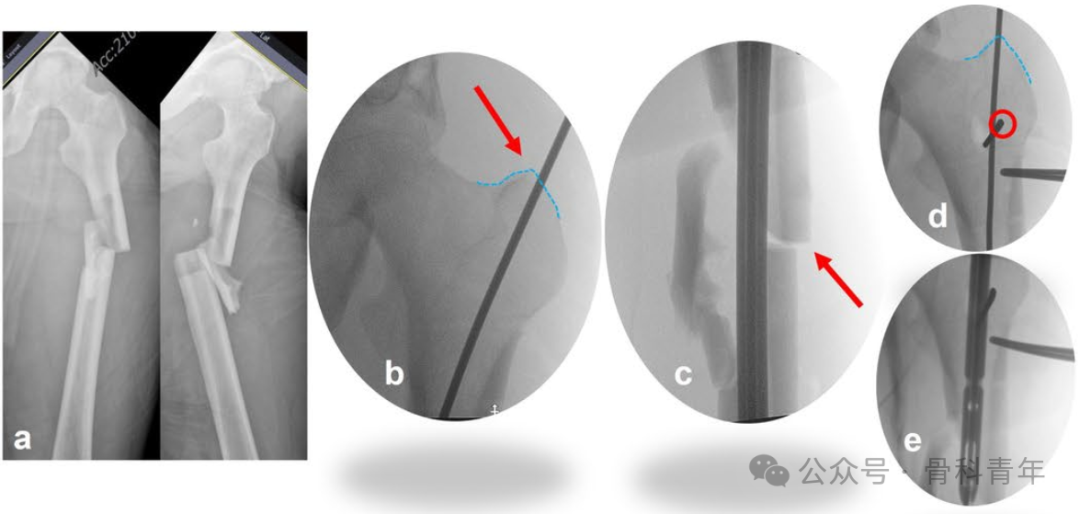

指征1:导针进针点位于大转子外侧。由于近端骨块在肌肉牵拉下出现内翻、内旋畸形,术中精准置入导针比较困难。如术中导针置入大转子间外侧,则近端骨块会出现内翻畸形,此时,需将导针进针点开口扩大,留出髓内钉内移空间,后在髓内钉可能置入方向的外侧,置入阻挡钉,纠正内翻畸形。

指征2:导针进针点准确,粗隆下内侧皮质粉碎,导致内翻畸形。粗隆下内侧皮质粉碎,失去对髓内钉的阻挡作用,导致近端骨块内翻。因此在术中,应在小粗隆水平髓内钉通道位置的内侧置入阻挡钉,纠正内翻。

指征3:在侧位上,存在向前成角。除在冠状面的成角外,矢状面上的移位可以在侧位上体现。近端骨块在髂腰肌和外展肌群的牵拉下,容易向前成角。此时,需要将阻挡钉置于髓内钉前进方向的后方,纠正向前成角。